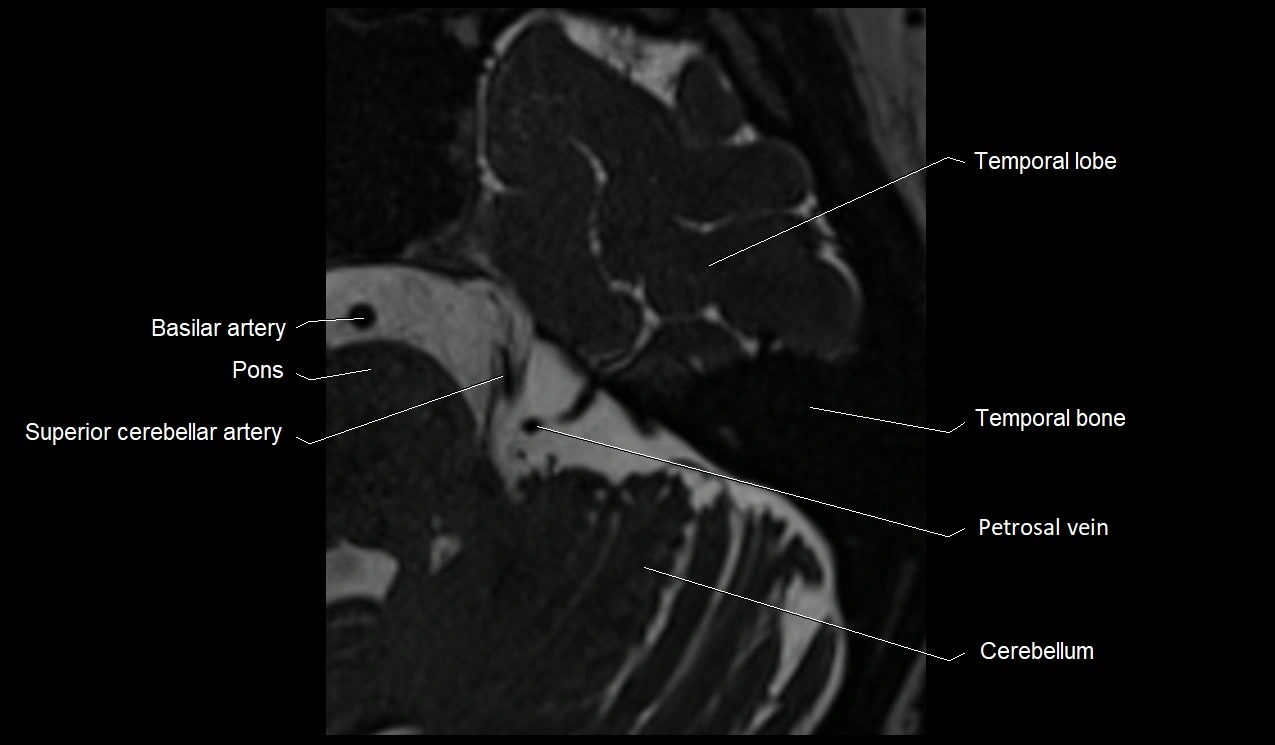

MRI images

image